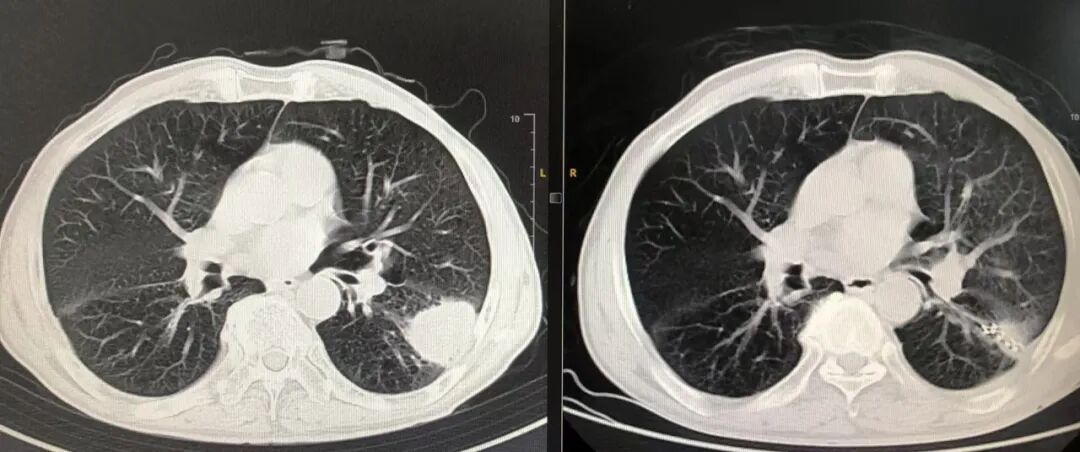

考虑到病情的严重,治疗刻不容缓,在主任医师王海英团队的耐心解说和精心策划下,张大娘最终接受了肿瘤内碘125粒子植入术的治疗方案。经过充分的术前准备,王海英带领团队在CT导向下,成功将放射性碘125粒子精准植入到张大娘左上肺的肿瘤内。这些粒子将在肿瘤内部持续发挥“放疗”作用,有效时间约半年。术后第二天,张大娘便能够自由下床活动,状态恢复良好,让隔壁床的患者都感到惊讶。

图片VxG帝国网站管理系统

▲张大娘术前术后对比图VxG帝国网站管理系统

后续随访评估显示,张大娘和周大爷的病灶均有明显缩小,疗效显著。这一创新疗法不仅为患者带来了身体上的改善,更重要的是给予了他们后续治疗的信心与希望。